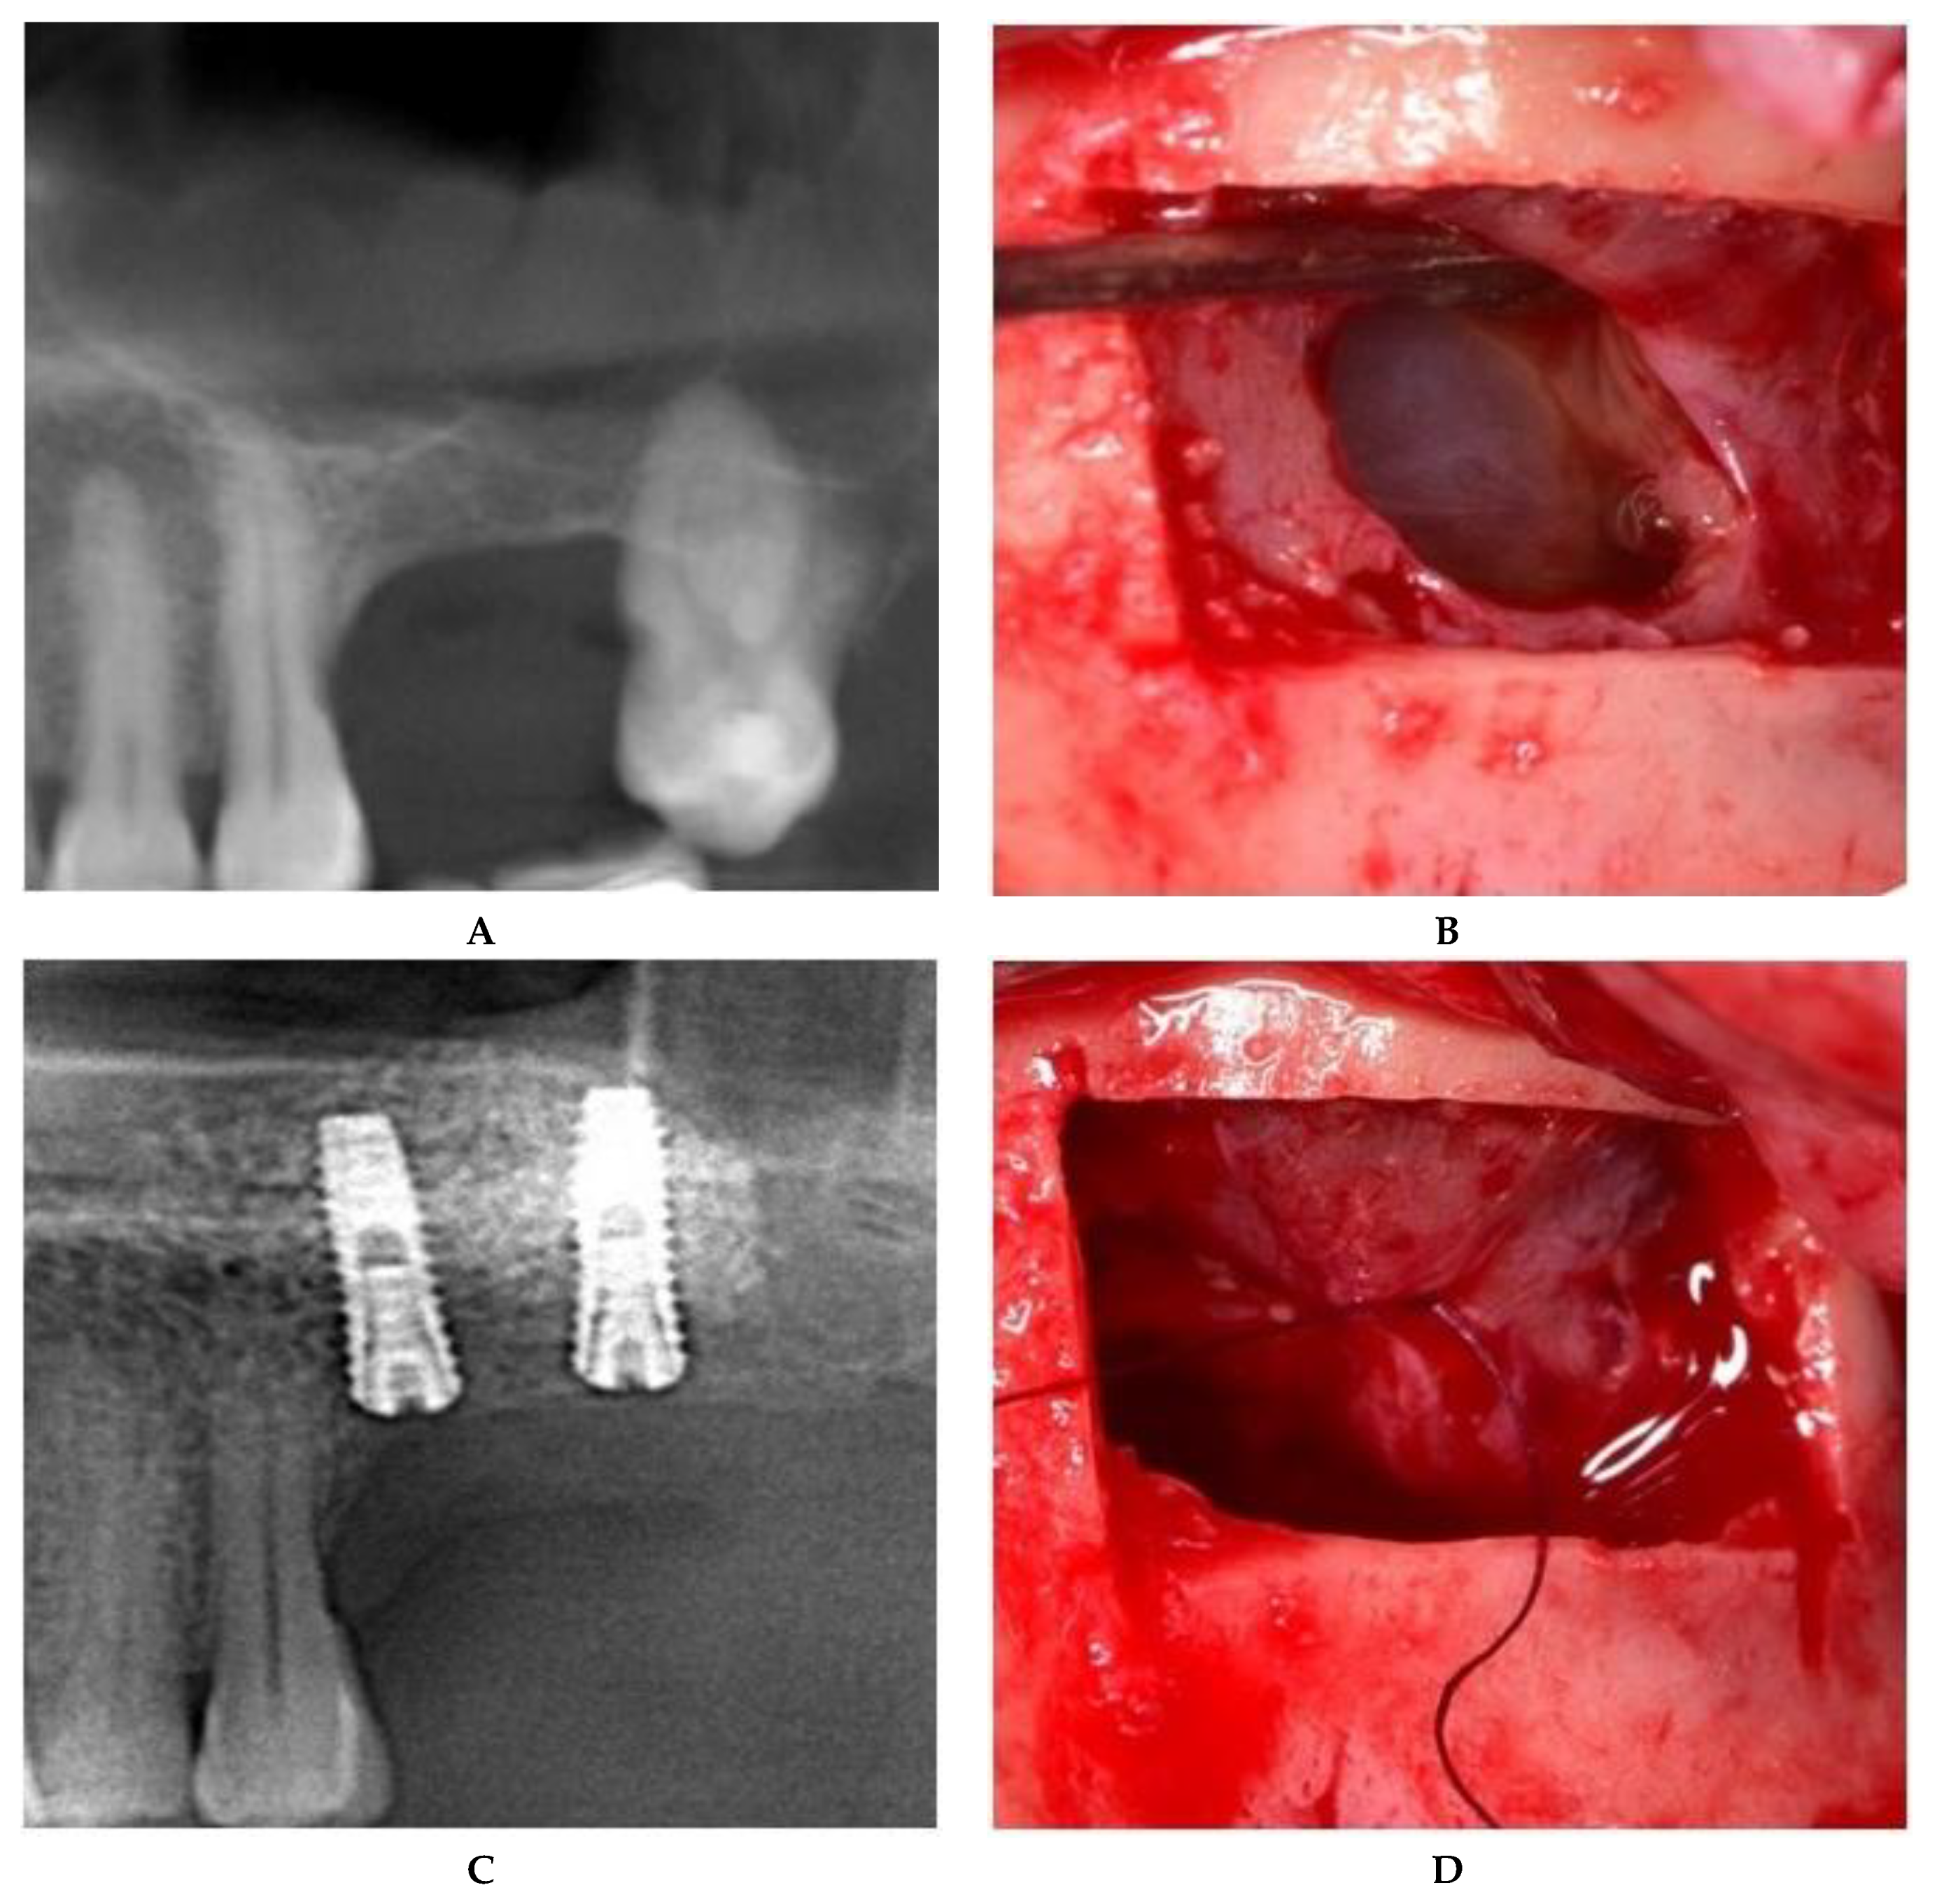

For large or multiple perforations, a single large pericardium membrane is placed in intimate contact on the elevated sinus membrane covering beyond the margin of the perforated area/s. In this study, collagen membranes with a low resorption rate (CopiOs Pericardium Membrane, Zimmer Biomet, Warsaw, IN, USA) were used to seal the perforated Schneiderian mucosa (Figure 1).

Large (more than 10 mm) or multiple perforations usually occur in thin, fragile sinus membranes with reduced elasticity. The remaining mucosal tissue between multiple perforations makes it impossible to suture without additional strain on the membrane. In addition, medially positioned perforations from the osteotomy contour lead to reduced access and visibility, which hindered correct suturing of the mucosal margins. For these reasons, the treatment of choice in this type of Schneiderian membrane tear is to seal with a pericardium membrane in order to provide an inside lining (Figure 1).

Figure 1. Schneiderian membrane sealing technique with collagen membrane coverage. (A) Preoperative CBCT image. (B) Large, multiple Schneiderian membrane perforations. (C) Bone graft placed in the collagen membrane “pouch”. (D) Postoperative CBCT after implant placement.